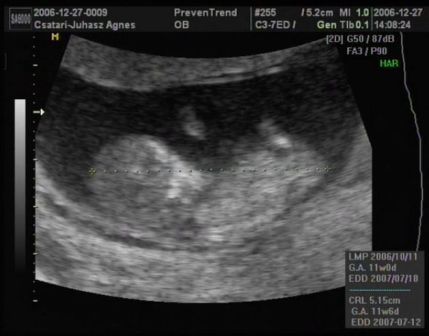

Ma voltam nyaki redő mérésen, integrált teszten. A nyaki redő 0.7 :D

A méretei alapján nem 11 hetes vagyok, hanem kb 1 héttel idősebb.

Rettenetesen ficánkolt, kaptam róla dvd-t is. Boldog vagyok, hogy megörökítettük!!! Hallottam a szive kalapálását és láthattam a kis kezeit, lábait... Velem volt a párom is, gondolhatjátok mennyire boldog volt ő is!

Rakok fel nektek képeket:

Kép Kép Kép Kép